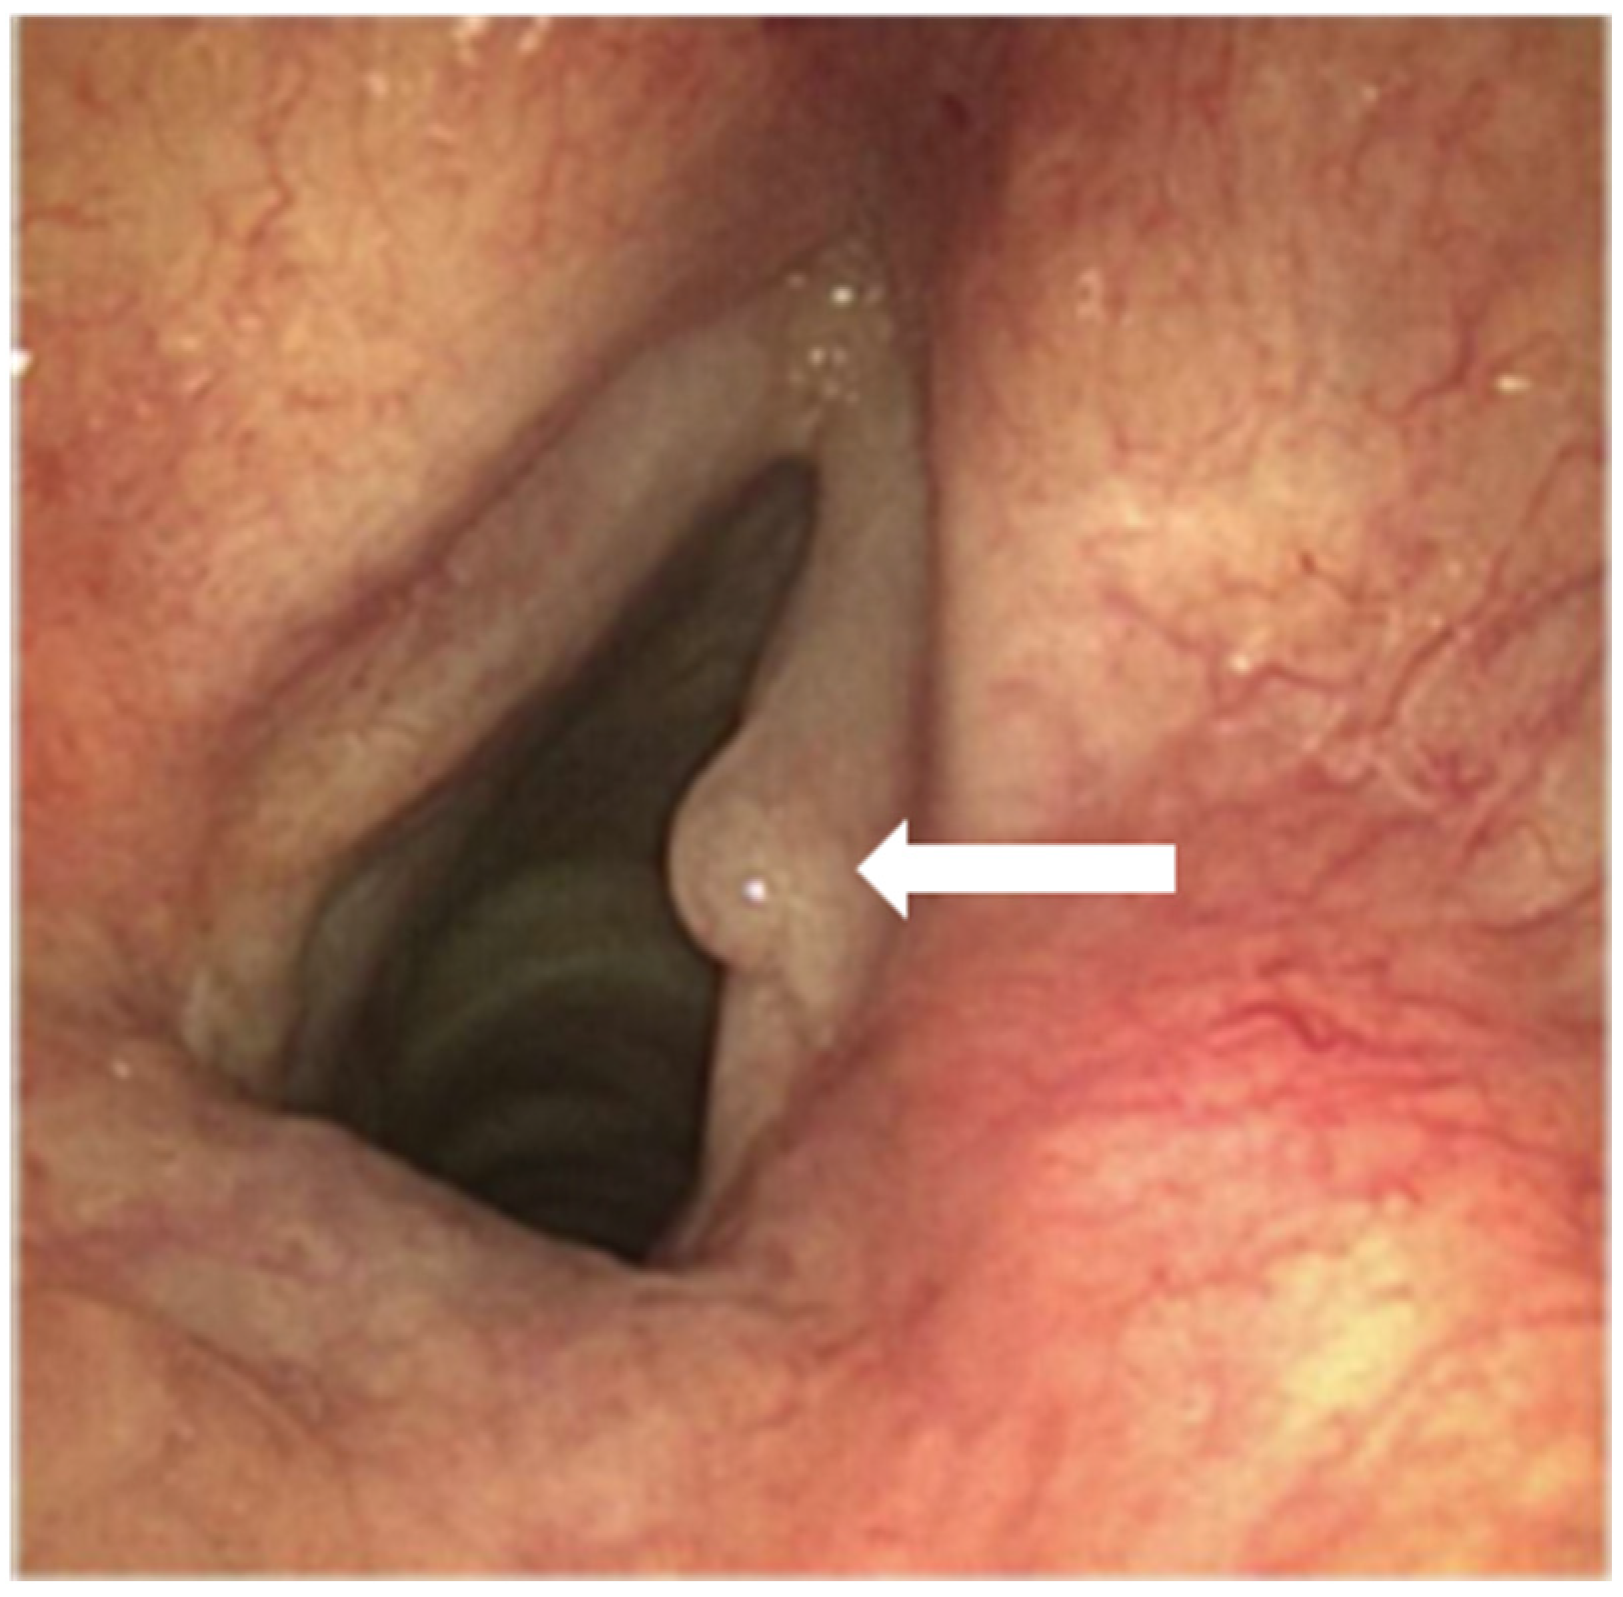

A flexible rhinolaryngoscopy showed an abnormal anatomy of the epiglottis (Figure 1). A laryngeal carcinoma, arising from the anterior side of the epiglottis and extending bilaterally into the aryepiglottic fold, was observed. The entire epiglottis was thickened and rotated to the left, with the vallecula completely filled up. The lateral pharyngeal wall, both arytenoids, and the false and true vocal cords were free of tumor on both sides. The vocal cords showed no abnormalities besides a hyperplastic, polyp-like spot (Figure 2). CT imaging showed that the carcinoma measured 26 × 25 mm axially and 18 mm sagittally. The CT scan obtained the following additional findings: “Filling of the vallecula on the right more than on the left, also involving the lingual side. Primarily right-sided involvement of the aryepiglottic fold at the cranial side. Involvement of the pre-epiglottic fat, with subtle bilateral cranial paralaryngeal fat involvement at the supraglottic level. No involvement of the (cartilaginous) thyroid or hyoid bone. No extension into the base of the tongue. No enlarged lymph nodes”. The histology of the sentinel lymph node in the neck would further determine the treatment algorithm.

Figure 1.

Visualization of the laryngeal carcinoma, arising from the anterior side of the epiglottis, by using a flexible rhinolaryngoscope (A,B).